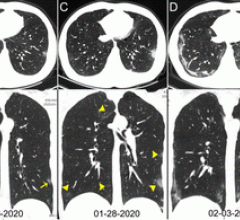

February 5, 2020 — In a special report published in the journal Radiology, researchers describe computed tomography (CT) ...

January 31, 2020 — One of the first imaging studies on the coronavirus (2019-nCoV) was published online today as ...